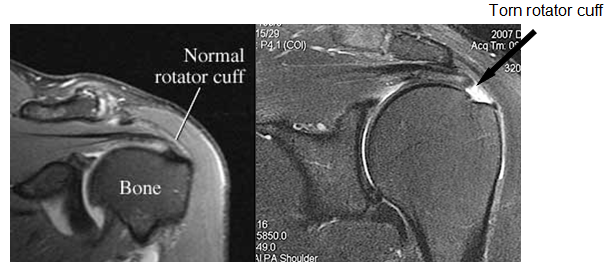

To diagnose a rotator cuff tear, your surgeon performs a thorough physical examination. He may request you for radiological investigations like Xrays or MRI scans. The first investigation is usually a Xray. Most of the times the X-rays turn out to be normal, except for a spur. This is because the soft tissues are not seen on the X-ray. MRI scans give us a very good idea of the rotator cuff tear. They can tell us the size and thickness of the tear, the condition of the muscles and also if the tear is old or new.